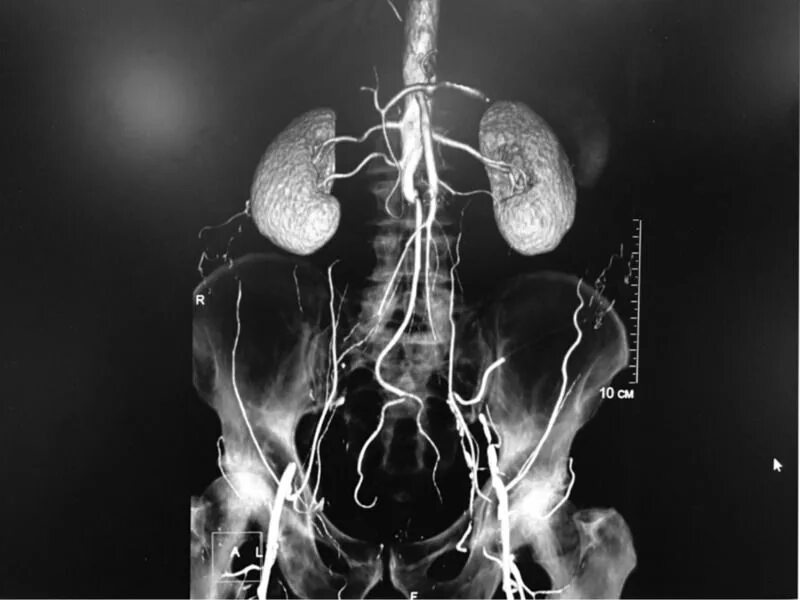

Стенты мрт